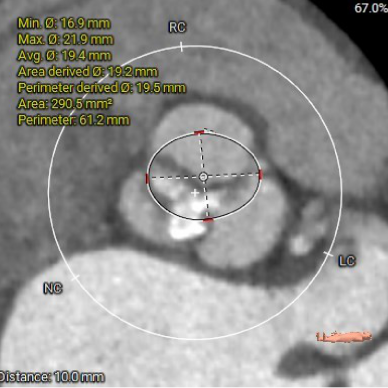

主动脉根部测量

1. Type 1 型二叶式主动脉瓣,瓣叶增厚伴中度钙化,L-N间钙化融合嵴,左室流出道呈敞口型;

3. 三窦大小不一,瓦氏窦、窦管交界内径偏小,升主动脉轻度扩张;左室腔内径尚可,心室壁未见明显增厚;

4. 瓣环水平夹角51°,主动脉弓夹角偏锐利,弓距偏小;